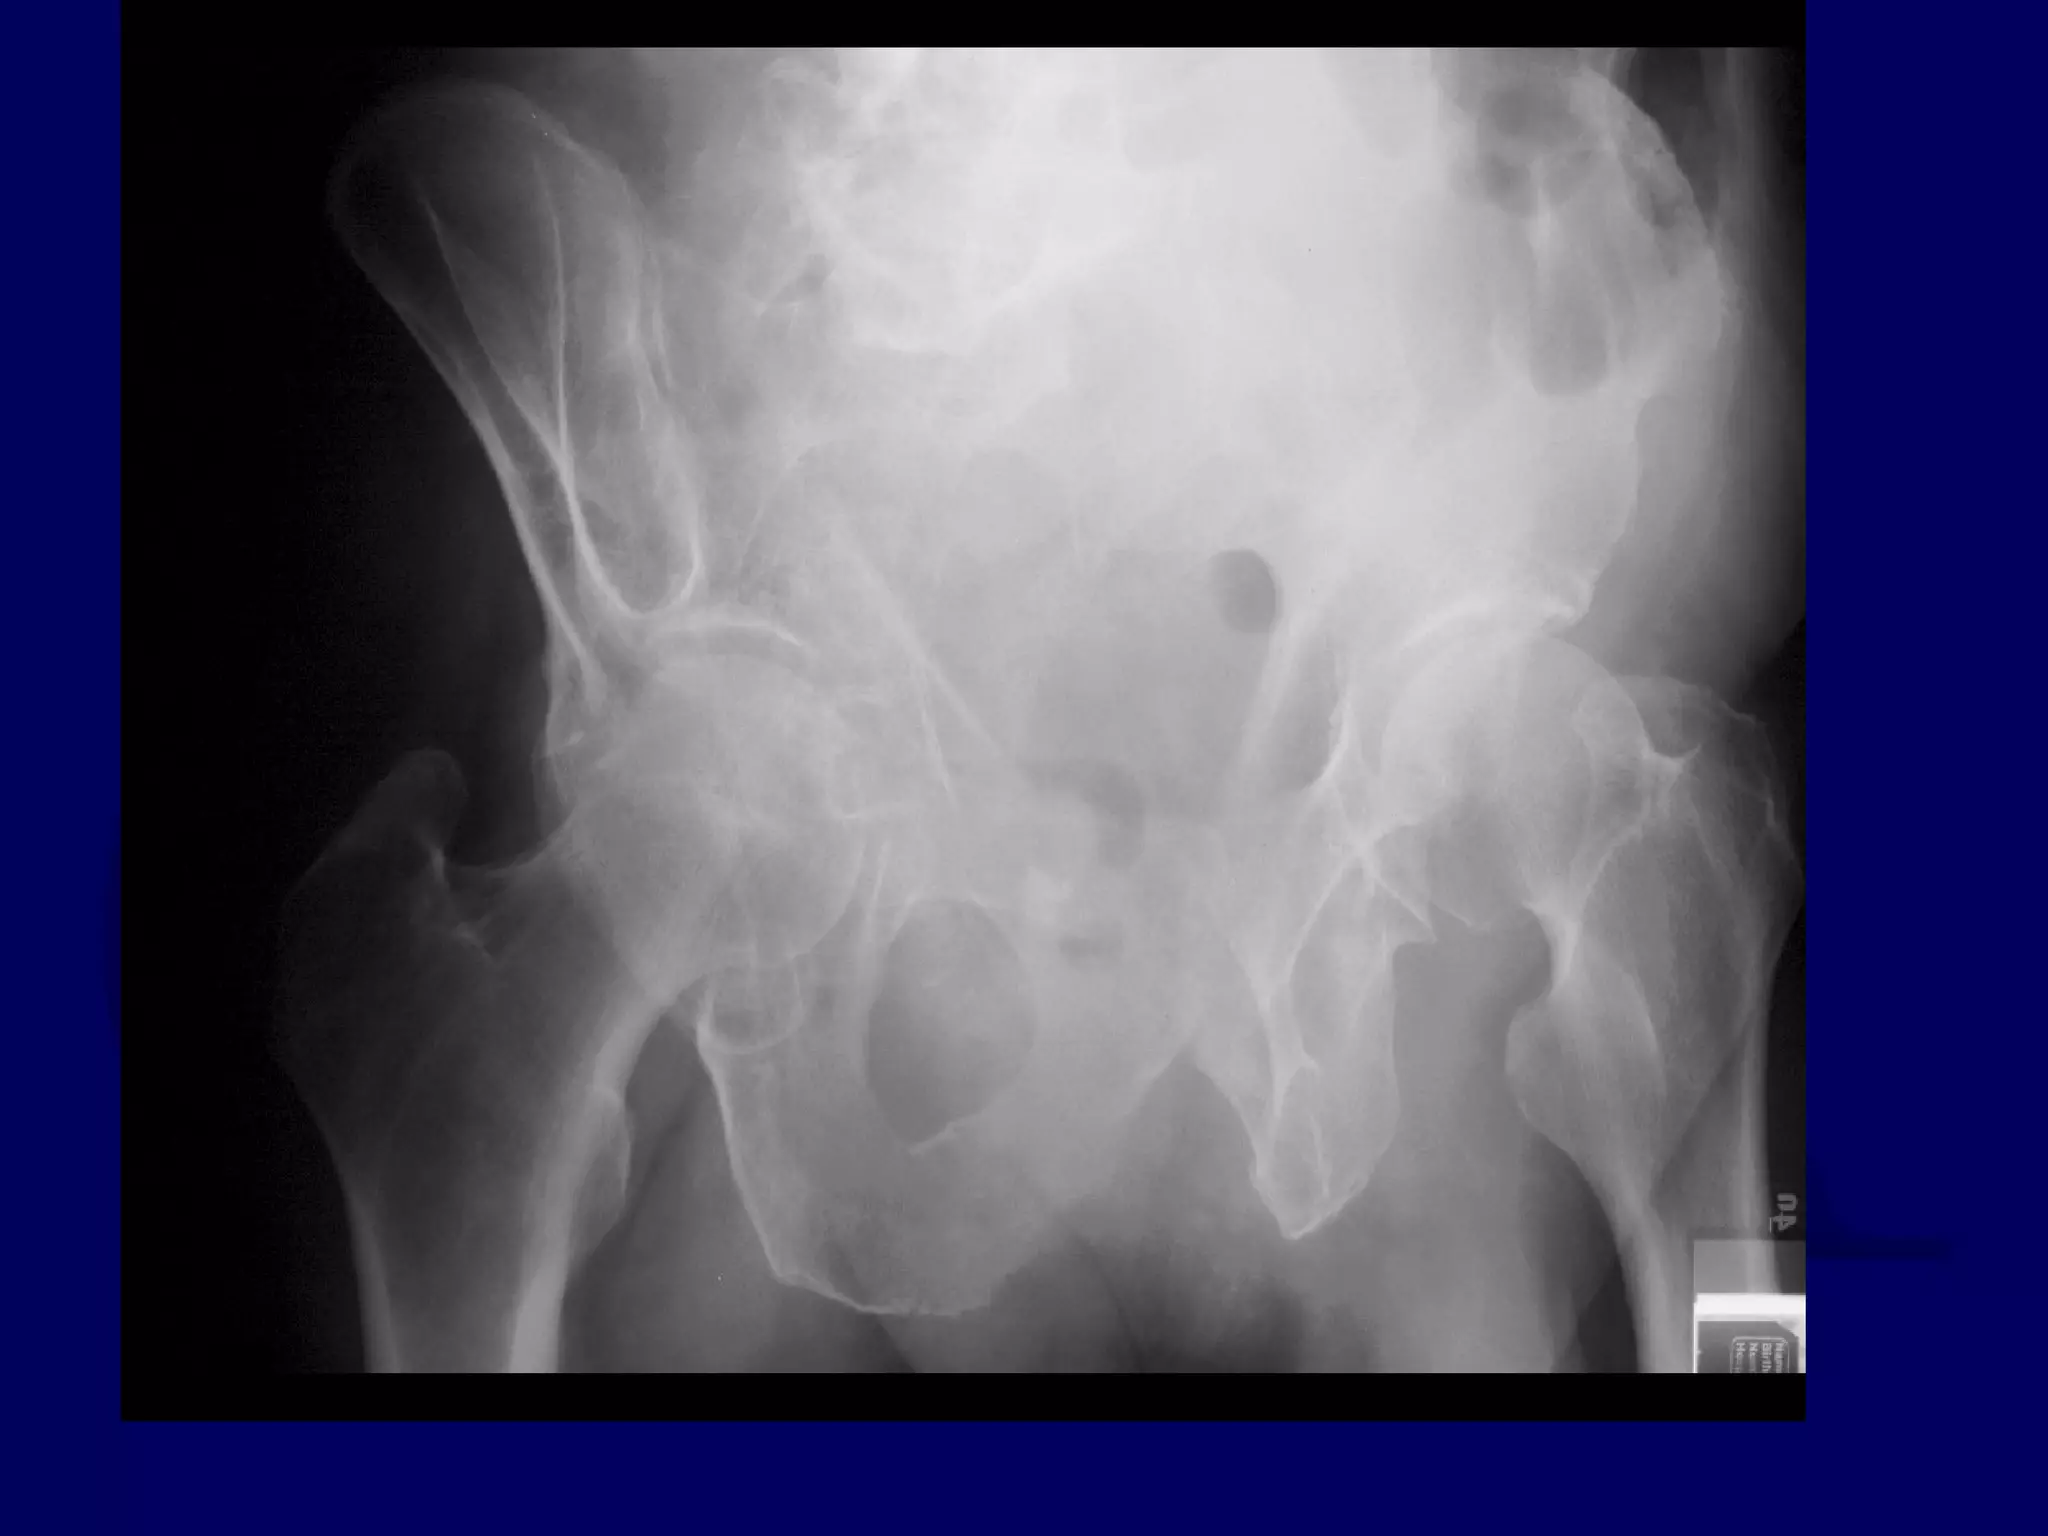

Both Column

Acetabular Fracture

18 Y.O. Female

Isolated Injury

R.C. 00.03.09

SPUR

SIGN